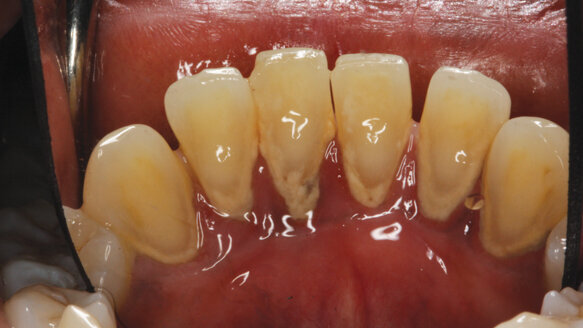

• Diabetes. Diabetic patients have a higher prevalence of periodontal disease and greater attachment and bone loss.18,19 Patients with diabetes, especially poorly controlled diabetes, will generally have a worse overall prognosis than patients who are not diabetic (Fig. 1).

• Crown-root ratio. Crown-root ratio is also a measure of attachment loss, especially when dealing with short roots. The example on this page demonstrates poor crown-root ratio related to a developmental anomaly in a patient with short roots (Fig. 2).